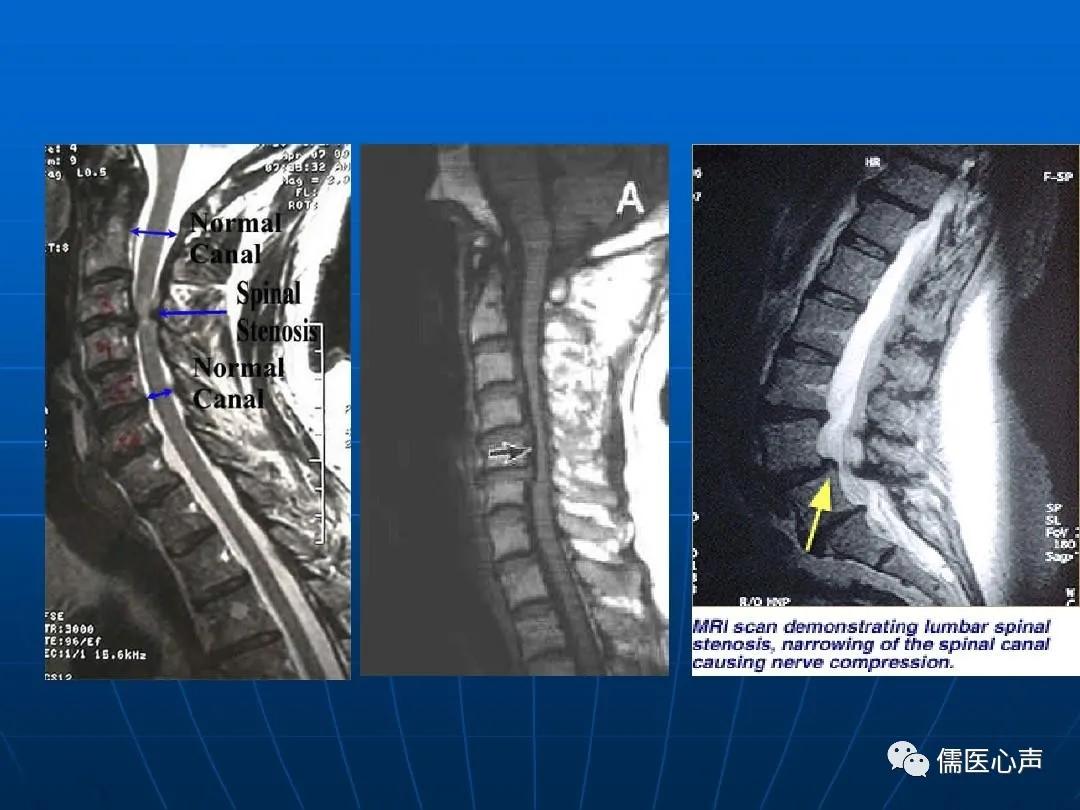

腰椎椎管狭窄症是指各种原因引起的腰椎骨与软组织(关节突关节、椎板、黄韧带、椎间盘等)发生形态与组织结构的变化,导致中央椎管、神经根管、椎间孔处狭窄,使神经根和(或)马尾神经受到压迫,引起一系列临床症状的疾病。 该病严重影响患者生活和工作,原本多见于老年人,但近年来出现了部分年轻化的趋势,这与人们的日常生活习惯有着不可分割的关系。

腰椎CT及MRI检查是目前最常用的检查方式。CT检查可显示椎管及根管断面形态,但不易了解狭窄全貌;MRI检查更可显示腰椎椎管的全貌。根据CT或磁共振等影像学结果,椎管横径或纵径小于13mm为相对狭窄,小于11mm为绝对狭窄。

有了影像学支持,才有了腰椎椎管狭窄症的诊断。